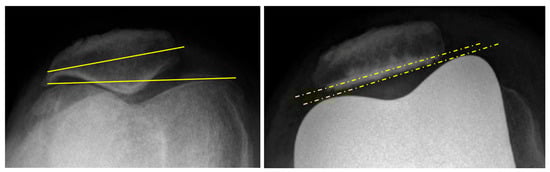

3.2. Patellar Tracking

| Patellar tilt (°) (mean ± SD) [Min; Max] | 4.4 ± 4.5 [0; 14] | 2.9 ± 3.2 [0; 11] | 0.146 |

| Patellar tilt > 5° | 14 (31%) | 4 (8.9%) | 0.016 |

| Patellar translation (mm) (mean ± SD) [Min; Max] | 0.6 ± 2.4 [0; 14] | 0.4 ± 1.4 [0; 6] | 0.763 |

| Patellar translation > 5 mm | 2 (2.4%) | 1 (2.2%) | 1.000 |